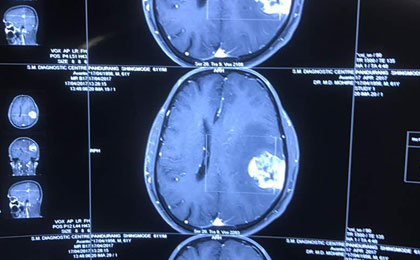

Brain Tumor Surgery  14/02/2019

frontal epidermoid post

• frontal epidermoid post

Huge Haemangioma PRE

• Huge Haemangioma PRE

Brainstem Glioma